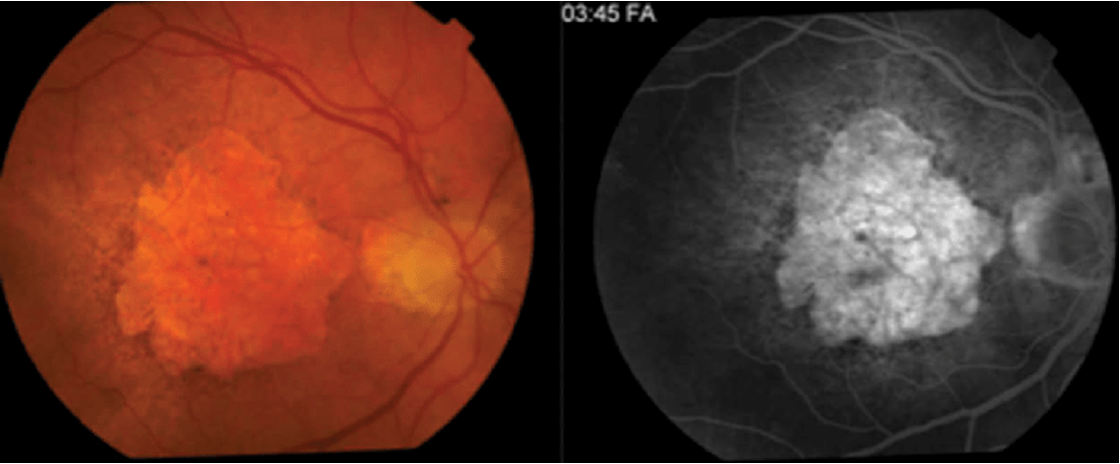

9

Q

A

End stage of wet AMD, a disciform scar.

Neovascular AMD with haemorrhage.